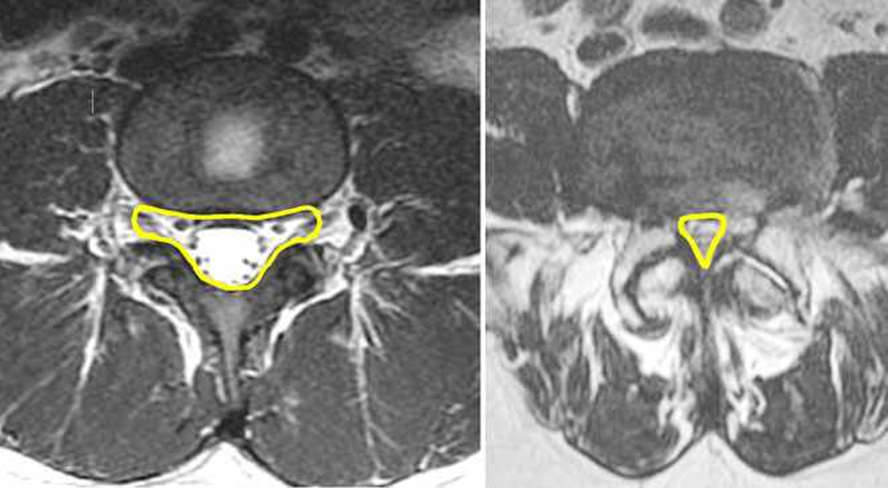

Omurgaların içerisinde omuriliğin geçtiği kanalın çapı bel, sırt, boyun bölgesinde farklılık gösterir. Bu kanalın çapı yüzde 25 daralmışsa hafif, yüzde 25-50 daralmışsa orta, yüzde 50 üzeri daralmışsa şiddetli dar kanal (spinal stenoz) adı verilir. Kanal darlığı; yaşla birlikte bağların kalınlaşması, kireçlenmelere bağlı kemik çıkıntılar, bel fıtığı, omurga kırıkları, kemik erimesine bağlı omurgaların çökmesi, tümörler ve ameliyat sonrası gelişen komplikasyonlara bağlı görülebilir. Dar kanal en çok bel bölgesinde L2-L5 omurlar arası ve boyunda C4-C7 omurları arasında görülür. Omurga ve içindeki yapılar; yani disk, bağlar, kemik yapı, sinirler veya damarların normalden daha fazla genişlemesi ve kanala bası yapması sonucu diğer yapılara kalan alanın daralması ile oluşur. Basit anlatımla içerisinden su akan bir hortum düşünün. Bu hortumun 2-3 yerde üzerine taş koyduğunuzda hortumdan geçen suyun az aktığını ve zorlandığını görürüz. Dar kanalda da benzer durum oluşur.

Medikal tedaviye cevap vermeyen, şikayetlerin şiddetli olduğu, özellikle kanal çapının 9 mm ve altında olduğu durumlarda cerrahi tedavi gereklidir.